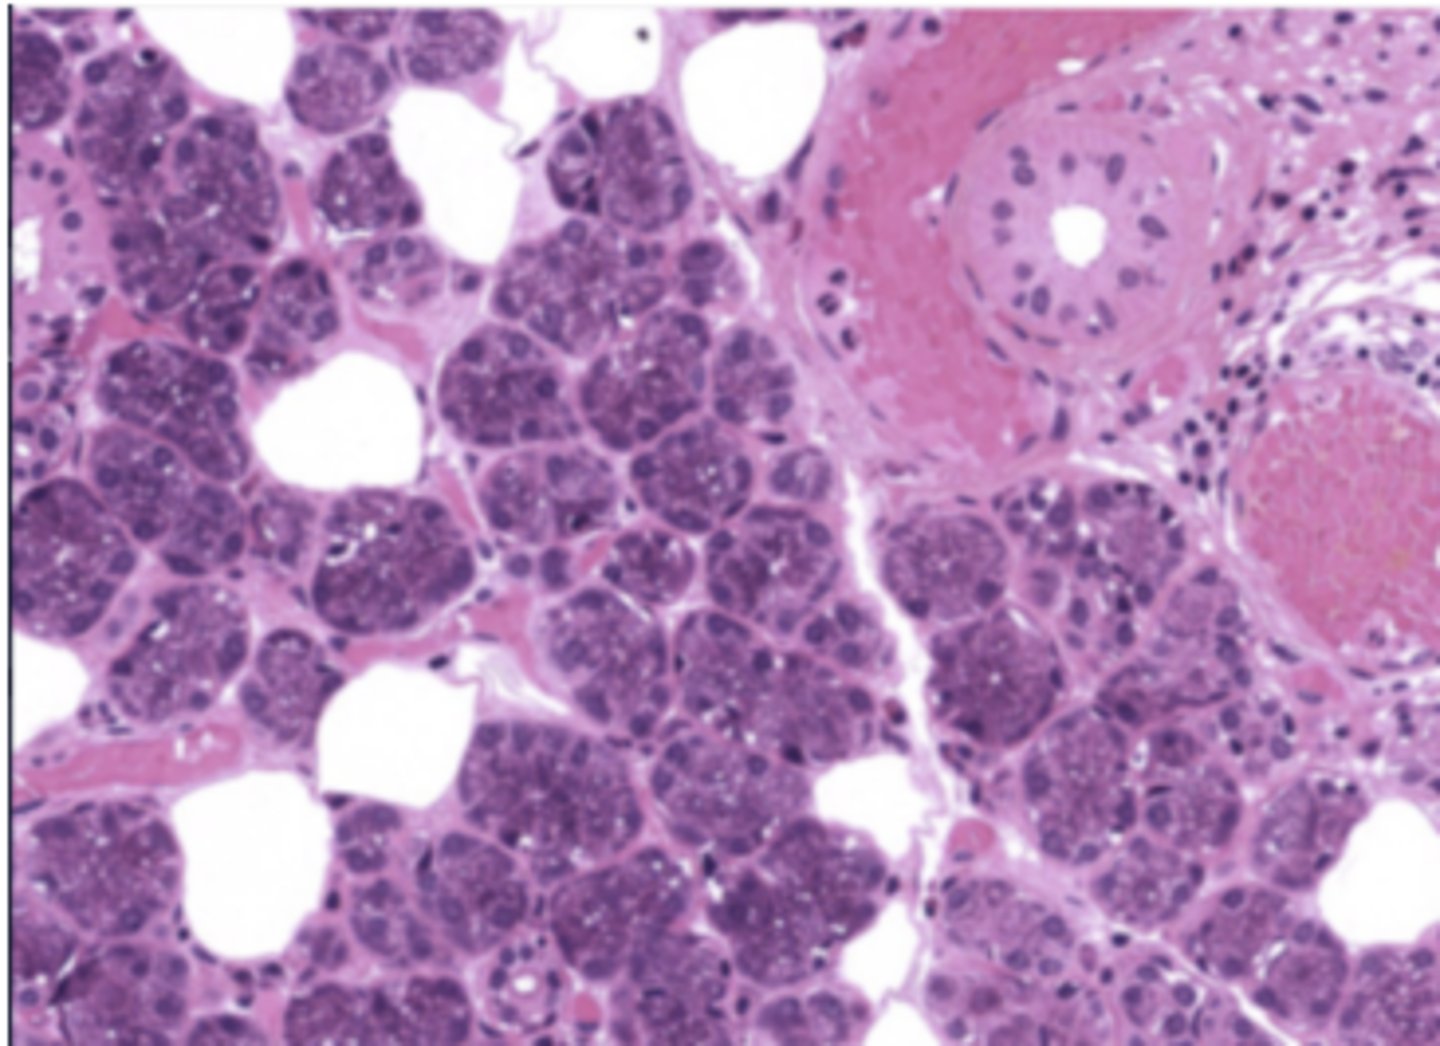

Pancreas

Centroacinar cells exclusively from which of the following organs?

green arrow = centroacinar cell